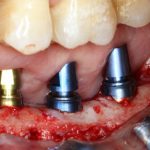

или имплантацией

или направленной костной регенерацией:

Откроем область операции и посмотрим, что там:

Вроде как, всё неплохо. Наверное, можно поставить имплантаты?

ну, или как-то так:

При этом, я хотел бы обратить ваше внимание на один важный момент. То, с чем вы сейчас работаете — не кость, в привычном нам гистолого-физиологическом понимании. Это костная мозоль вперемежку с графтом. Её свойства довольно сильно отличаются от того, что мы привыкли называть костной тканью. Поэтому при установке имплантатов соблюдайте максимальную осторожность и щадящий режим. Никаких диких торков, усилий, больших переходов между размерами фрез допускать нельзя. Будьте аккуратны.